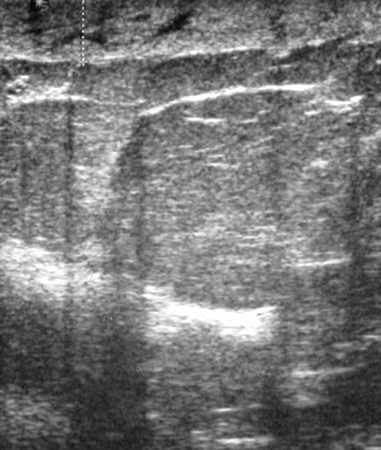

Imagen en ultrasonografía de un fibroadenoma

Cortesía del Dr. Lane Roland, University of Louisville; utilizada con autorización